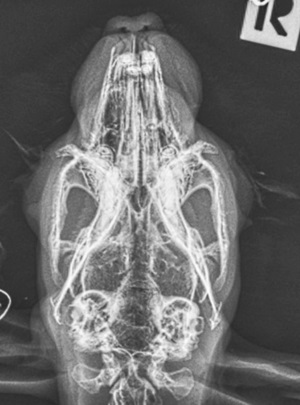

Am wichtigsten bei der Röntgenuntersuchung ist die dorsoventrale Aufnahme, d. h. das Kaninchen sitzt bzw. liegt gerade auf dem Bauch und der Schädel wird "von oben nach unten" geröngt. Auf die Weise können beide Mittel- und Innenohren nicht nur separat, sondern auch im Seitenvergleich beurteilt werden.

Wichtig ist eine absolut gerade Lagerung, da verkippte Aufnahmen Asymmetrien vortäuschen können. Hierfür hat es sich bewährt, das Kaninchen auf den Röntgentisch zu setzen, anschließend eine Mullbinde o. ä. über seinen Kopf zu spannen und den Kopf damit nach unten zu drücken, sodass das Kinn zwischen den Vorderbeinen auf dem Tisch zu liegen kommt. Die meisten Kaninchen tolerieren diese Lagerung völlig problemlos.

Mithilfe der Aufnahme kann insbesondere festgestellt werden, ob die normalerweise gut belüfteten Bullae tympanicae (Paukenhöhlenblasen) mit Sekret gefüllt, ihre Wände entzündlich verdickt oder Knochenauflösungen vorhanden sind.

Die Röntgendiagnostik liefert einen ersten Anhaltspunkt dafür, ob eine Oittis media / interna vorliegt. Eine Narkose ist hierfür nicht nötig und v. a. bei bereits geschwächten Tieren nicht zu empfehlen.

Gerade im Anfangsstadium einer Infektion ist es allerdings möglich, dass Veränderungen auf Röntgenbildern noch nicht sichtbar sind. Selbst bei Kaninchen, die bereits hochgradige neurologische Symptome zeigen, können die Mittelohren röntgenologisch noch unauffällig wirken - während sie im CT bereits deutlich sichtbar mit Sekret gefüllt sind.